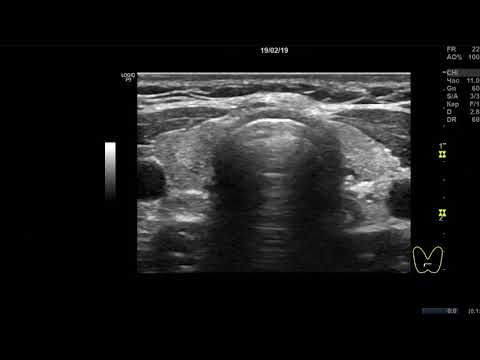

Клинический случай 8. (УЗИ Щитовидной Железы ) доктор А.В. Ушаков

УЗИ диффузного процесса щитовидной железы с зобом 3 ст. УЗ-признаки тотального диффузного зоба щитовидной железы до 3 ст., с малыми явлениями мелко-долькового деструктивного преобразования, малой лимфоцитарной инфильтрацией и умеренным отёком стромы. Напряжение ткани железы (по интенсивности и скорости кровотока) в значительной степени усилено. Ткань железы, выглядящая относительно полноценной гормонообразующей (при этом с изменениями), составляет около до 90%.